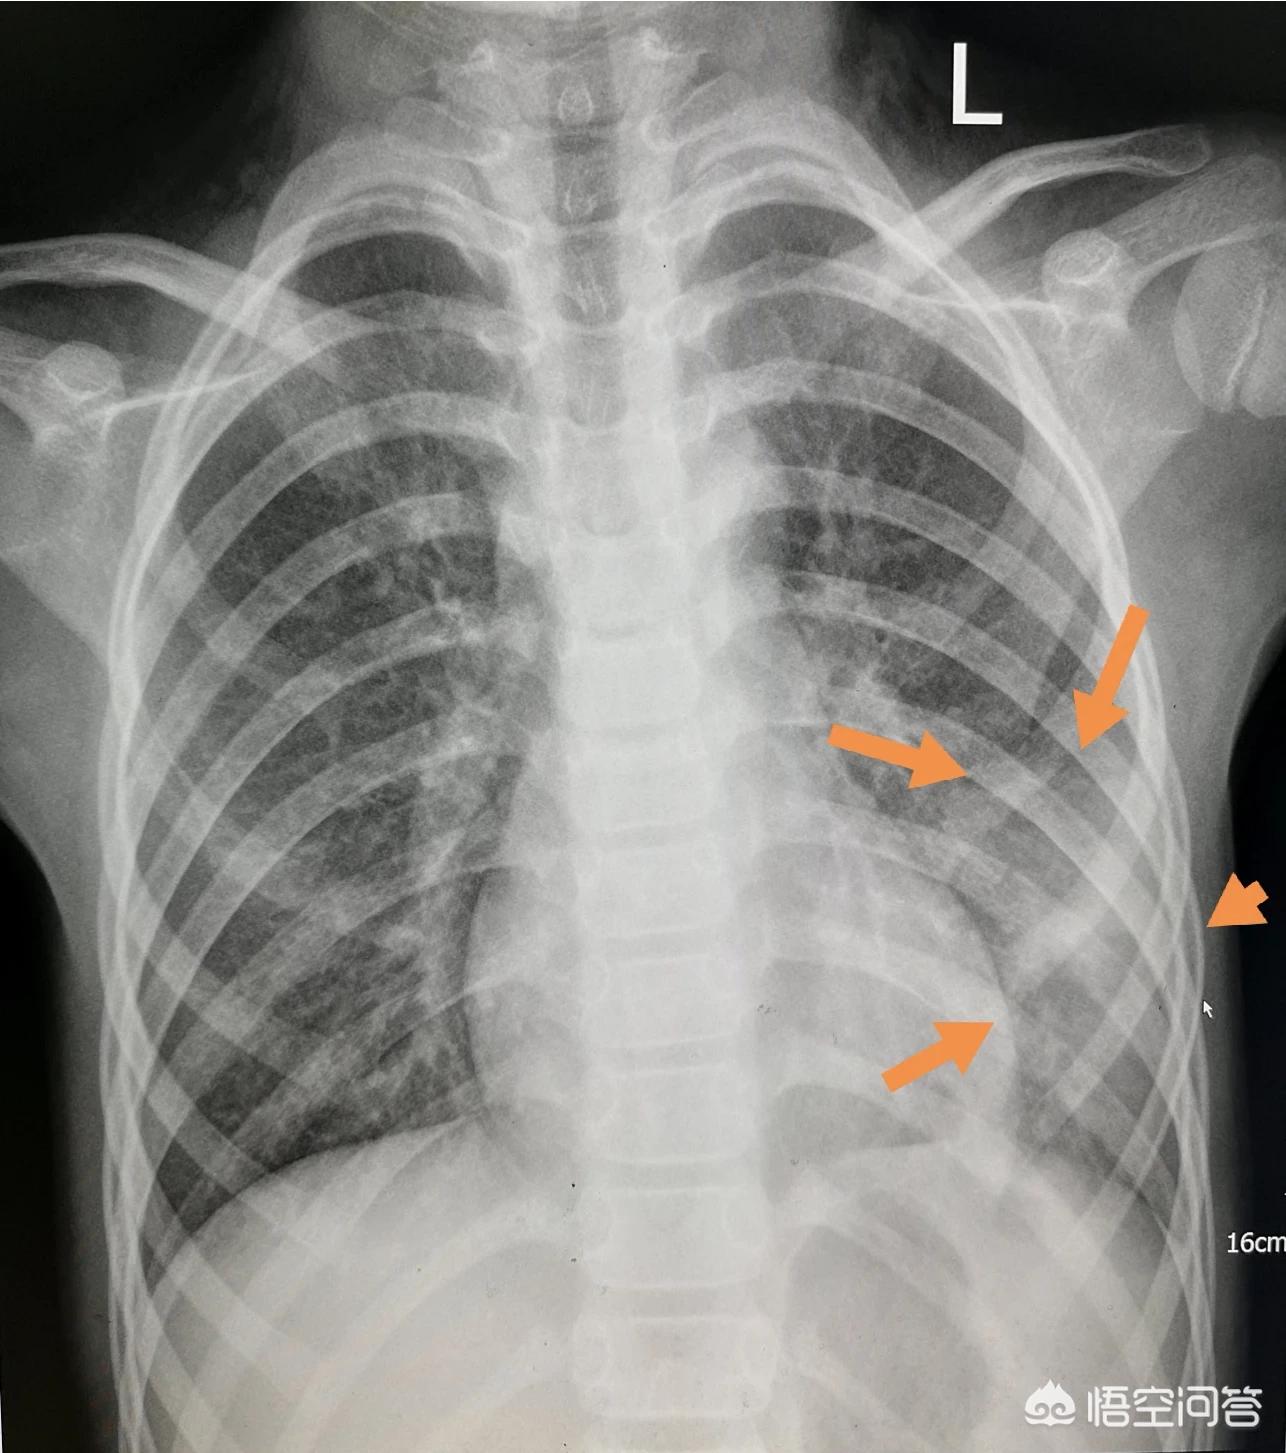

这个小女孩感冒好几天了,咳嗽越来越厉害,有时甚至能引起呕吐,但只是发热一天。

拍胸片发现左侧肺炎已经很明显了(片子上看到大片雾蒙蒙的实变影,提示病程在一周左右),需要马上抗生素治疗。

孩子的妈妈还念叨一句,一直以为只要不发热就没事,昨天开始发热,才有点担心。

好在治疗挺及时,使用的抗生素也很敏感,六天以后复查炎症已经基本吸收了: